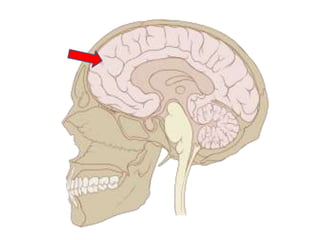

Ways of thinking about the brain

• Left to right

• Top to bottom

• Front to back